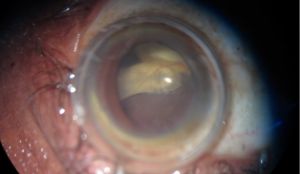

Surgical extraction of an armillifer from the anterior chamber. See the characteristic peristaltic movements of the parasite while it is removed through a clear corneal incision.

In the eye, larvae of Pentastomidae reside with a decreasing frequency in the anterior chamber, ocular adnexa, or the posterior chamber.[1] A recent case report also suggests an intracapsular location. [21] Depending on their location, they can manifest in different ways and/or induce:

- Annulated foreign body, eventually with peristaltic motion, in the anterior chamber [1]

Surgical extraction is the preferred treatment in case of ocular involvement, an early removal of the parasite being a factor of better prognosis, as it minimizes the exposure of the eye to inflammatory reactions and mechanical alterations related to the presence of larvae.[1] Nymphs can be removed through corneoscleral/limbal incisions, vitrectomy, iridectomy or lens extraction. [1][21]